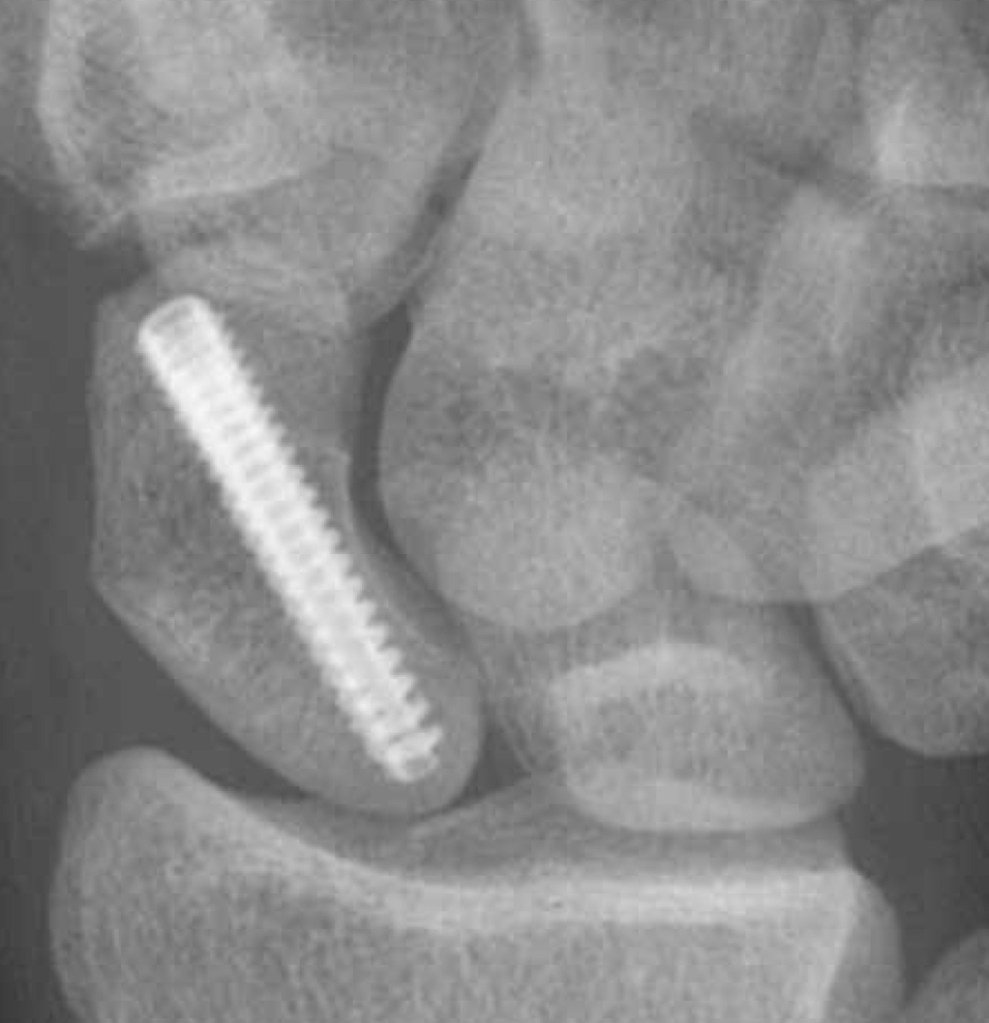

Surgery – Where symptoms are causing a problem, surgery is usually recommended. The operation involves taking a piece of bone from either the pelvis or the forearm (from a place where it will not be missed!) and placing it between the ends of the scaphoid bone. Sometimes a vascularised bone graft (a piece of bone with a small blood supply) may be suggested. For some cases, this type of bone graft may aid healing. The bone is then ‘fixed’ with a screw which holds everything in place until the bone heals. The screw is placed inside the bone, and usually stays there forever.